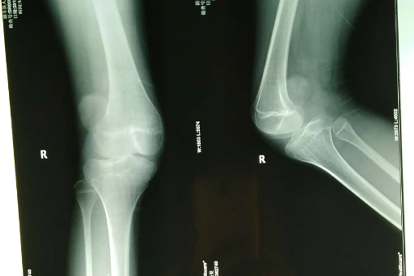

复发性髌骨脱位吃什么食物好

复发性髌骨脱位患者可适量吃高钙食物、优质蛋白食物、富含维生素D食物、富含胶原蛋白食物、富含抗氧化物质食物等,有助于骨骼和关节健康。若存在炎症反应或需手术干预,应遵医嘱配合药物治疗。